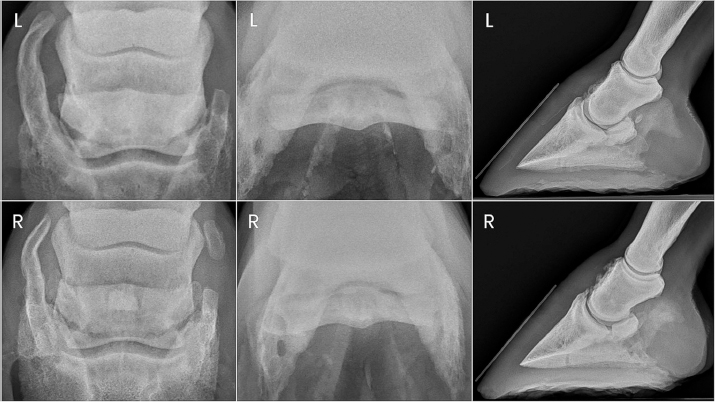

Fig. 3. Antemortem radiographs and postmortem MRI images of horse one showing bilateral navicular bone fractures, DIPJ hyperextension, and DDF tendon compromise.

Horse 1 remained pasture sound until day 84 post-PDN when he was presented for an abnormal gait with both toes displaying a mild dorsal elevation off the ground when weight bearing. Radiographs of the digits revealed parasagittal fractures of both forelimb navicular bones with hyperextension of both DIPJs (Fig. 3). Severe fiber pattern disruption of the DDF tendon was noted on ultrasound of both forelimb palmar pastern regions suggestive of severe DDF tendinopathy or rupture. Humane euthanasia was elected due to the severity of the pathology and poor prognosis. Postmortem magnetic resonance imaging (MRI) was performed on the forelimbs, which identified marked navicular bone degeneration with obliquely oriented, complete fractures of the lateral quarter of the navicular bone bilaterally, complete rupture of the DDF tendon extending from the distal aspect of the first phalanx to the navicular bone in the right forelimb, and nearly complete rupture of the DDF tendon in the left forelimb (Fig. 3). Additional findings of note in both forelimbs were hyperextension of the DIPJ, significant navicular bursitis with probable bursal adhesions, and desmitis of the impar, collateral sesamoidean, and distal digital annular ligaments.